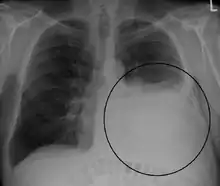

A pleural effusion appears as an area of whiteness on a standard posteroanterior chest X-ray.[12] Normally, the space between the visceral pleura and the parietal pleura cannot be seen. A pleural effusion infiltrates the space between these layers. Because the pleural effusion has a density similar to water, it can be seen on radiographs. Since the effusion has greater density than the rest of the lung, it gravitates towards the lower portions of the pleural cavity. The pleural effusion behaves according to basic fluid dynamics, conforming to the shape of pleural space, which is determined by the lung and chest wall. If the pleural space contains both air and fluid, then an air-fluid level that is horizontal will be present, instead of conforming to the lung space.[13] Chest radiographs in the lateral decubitus position (with the patient lying on the side of the pleural effusion) are more sensitive and can detect as little as 50 mL of fluid. Between 250 to 600mL of fluid must be present before upright chest X-rays can detect a pleural effusion (e.g., blunted costophrenic angles).[14]

Massive left-sided pleural effusion (whiteness) in a patient presenting with lung cancer. Massive left-sided pleural effusion (whiteness) in a patient presenting with lung cancer.

Massive pleural effusion, later proven to be hemothorax in a South Indian male. Massive pleural effusion, later proven to be hemothorax in a South Indian male.